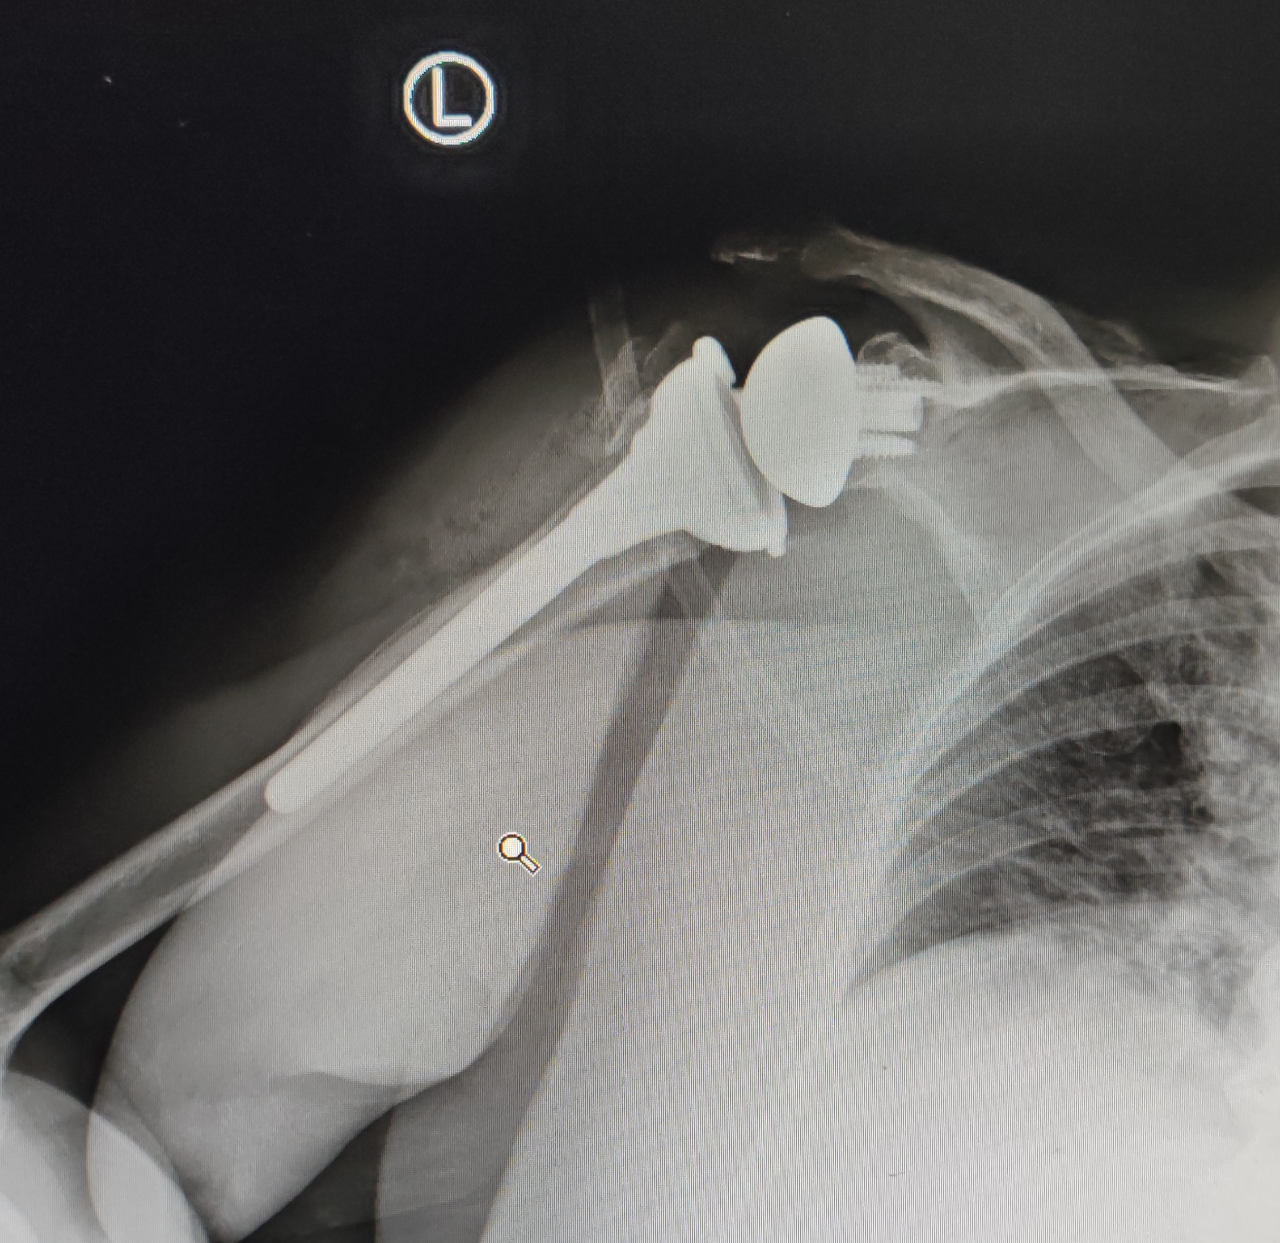

六、解剖型全肩关节置换术(Anatomical total shoulder replacement, ATSR)与全反式全肩关节置换术(Reverse total shoulder replacement, RTSR)。ATSR与RTSR是解决肩关节退变与骨折的重要方法,但其手术技术具有一定的难度、有一定的学习曲线。在以色列,我更为系统地学习了ATSR与RTSR手术技术,对肩关节置换有了更深入的掌握与理解。